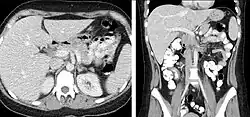

CT is an accurate technique for diagnosis of abdominal diseases like Crohn's disease,[69] GIT bleeding, and diagnosis and staging of cancer, as well as follow-up after cancer treatment to assess response.[70] It is commonly used to investigate acute abdominal pain.[71] Non-enhanced computed tomography is today the gold standard for diagnosing urinary stones.[72] The size, volume and density of stones can be estimated to help clinicians guide further treatment; size is especially important in predicting spontaneous passage of a stone.[73]

Vascular Imaging

Computed tomography angiography (CTA) is a type of contrast CT to visualize the arteries and veins throughout the body.[111] This ranges from arteries serving the brain to those bringing blood to the lungs, kidneys, arms and legs. An example of this type of exam is CT pulmonary angiogram (CTPA) used to diagnose pulmonary embolism (PE). It employs computed tomography and an iodine-based contrast agent to obtain an image of the pulmonary arteries.[112][113]